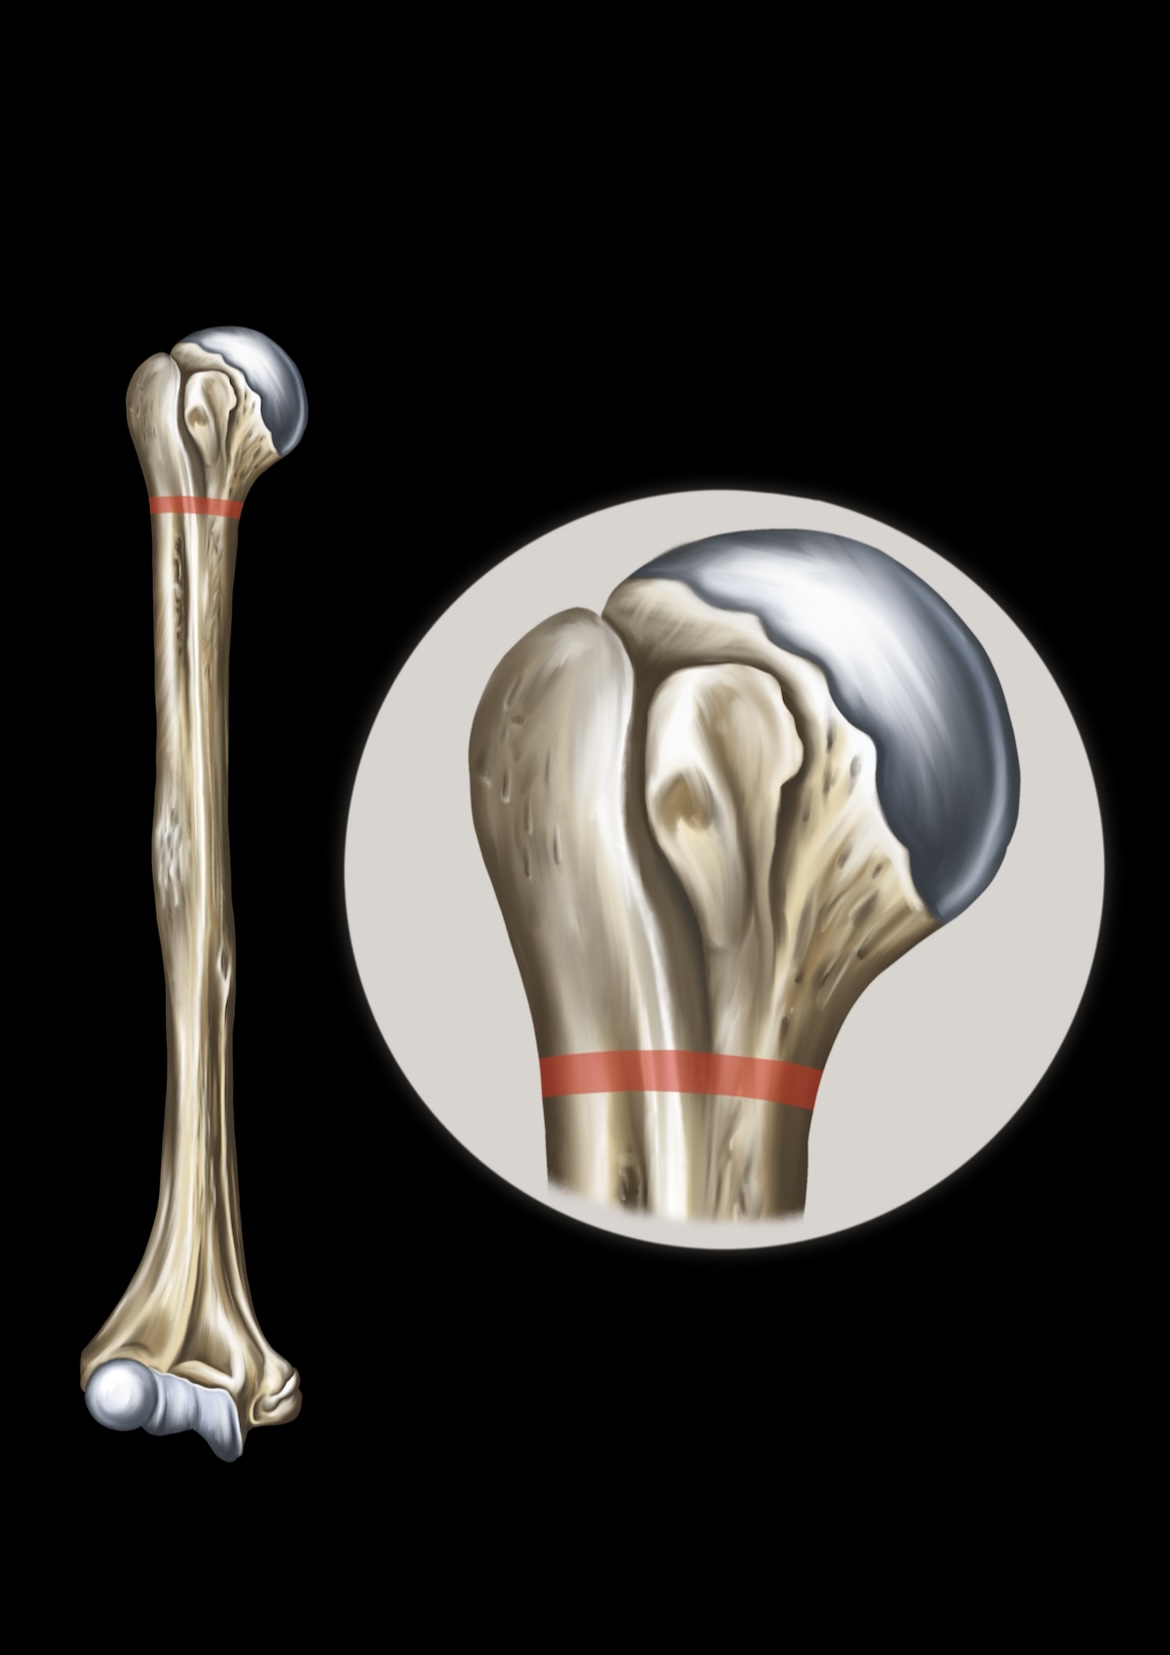

Surgical Neck of Humerous

Humerus

Head of the Humerus

Greater Tubercle

Lesser Tubercle

Intertubercular Groove

Deltoid Tuberosity